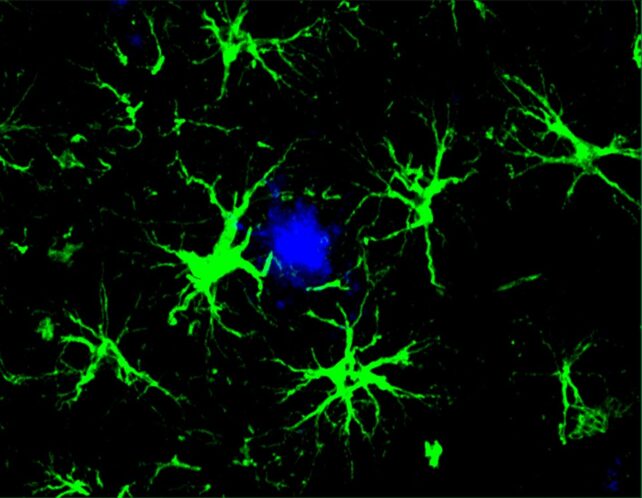

In the new study, researchers focused on star-shaped brain cells called astrocytes, which they engineered to hunt down the amyloid beta proteins associated with cognitive decline in Alzheimer’s.

“This study marks the first successful attempt at engineering astrocytes to specifically target and remove amyloid beta plaques in the brains of mice with Alzheimer’s disease,” says senior author Marco Colonna, pathologist at Washington University in the US.

Astrocytes normally perform a variety of important duties in the brain, including housekeeping, but this technique harnesses their collective power and leverages it against amyloid beta proteins.

Upon receiving this new assignment, astrocytes became singularly focused on clearing out amyloid beta plaques, a task at which they proved adept.

By six months of age, mice predisposed to amyloid beta accumulations tend to have heavy concentrations of these plaques in their brains. Those given the new treatment in their youth, however, had no such plaques when they reached this age, the study found.

Even in older mice whose disease was already underway, the treatment was associated with improvement. Older mice who received the gene therapy at six months of age had about half as many plaques by nine months as those in an age-matched control group, which received a virus missing the CAR gene.